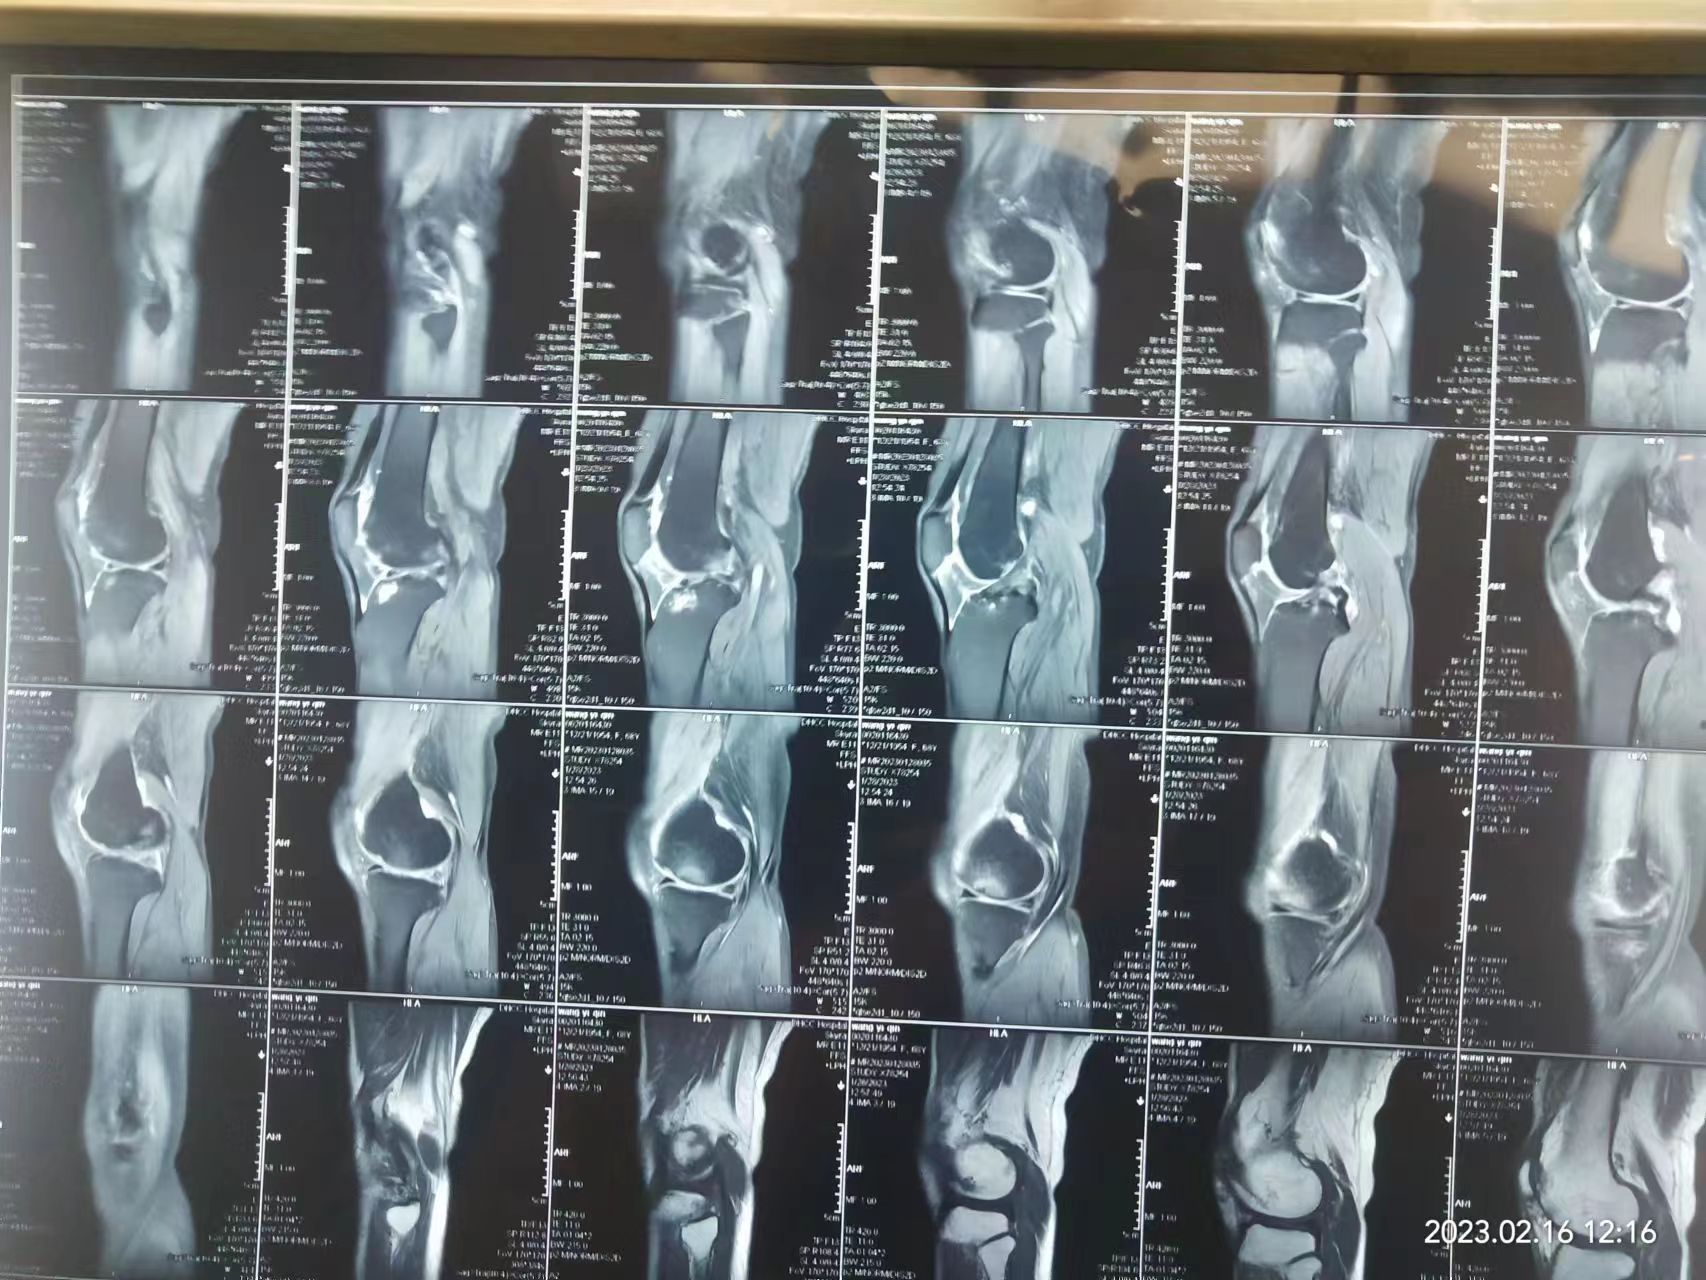

我院骨科专家团队接诊后,通过细致的专科检查发现王阿姨患有严重的右膝关节退行性病变,常规保守治疗已难以达到理想的治疗效果,建议做行人工膝关节置换术,才能恢复膝关节的功能,解除多年疼痛、行走不便困扰,提高生活质量。

王阿姨和家属沟通后,同意做手术。我院骨科专家团队立即开展病例讨论,结合王阿姨的病情和自身实际情况,科室详细为王阿姨量身定制了个体化的手术方案及康复计划。 经过细致的术前准备,由我院骨科主任医师丁建中带领骨科技术团队,在手术室、麻醉科默契配合下,为王阿姨成功实施行人工膝关节置换术。